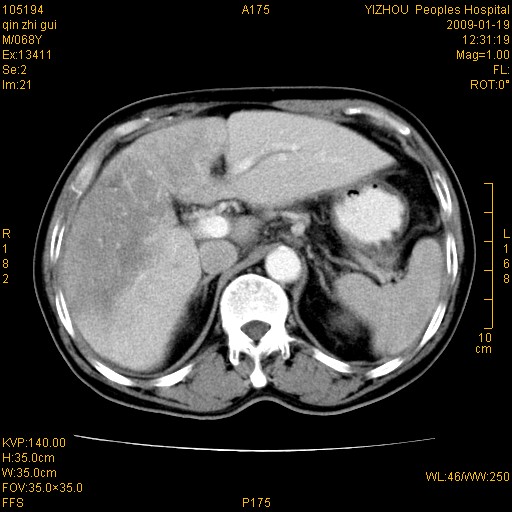

以下是引用随光逐影在2009-1-21 16:11:00的发言:[br]1)考虑肝右叶肝癌并肝静脉及门静脉瘤栓形成。2)肝硬化,少量腹水。3)胆囊炎。4)右侧少量胸腔积液。

病灶外缘凹凸不平,平扫低密度,增强动脉期有强化,门脉早显,静脉期及延期呈延迟强化,结合病史考虑右肝前叶巨块型肝癌可能性大,强化表现不除外胆管细胞癌